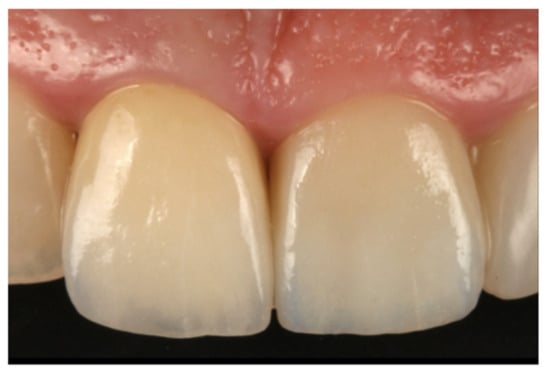

- Treatment with single zirconia crowns on teeth prepared with BOPT obtained an accumulated survival rate of 97.2%. Accordingly, the incidence of biological or mechanical complications was not statistically significant and the restorations presented good behavior over the 6-year follow-up.

- Teeth treated with this technique presented improved plaque indices, stable probing depths, increased gingival thickness, and stable gingival margins over the 6-year follow-up.

- Treatment with a fixed prosthesis using the BOPT technique has a positive impact on patient satisfaction, especially in cases concerning the re-treatment of old fixed prostheses. This fact is due to the esthetic improvement not only of the restoration but also of the surrounding tissues, as it improves gingival quality by thickening the tissue, thus preventing gingival recession.